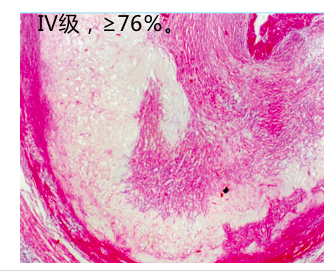

这三种成分的含量和分布随斑块的变化有所不同。典型病变的发生发展经过4个阶段,即:脂纹(fatty streak)---纤维斑块(fibrous plaque)---粥样斑块(atheromatousplaque),亦称粥瘤(atheroma)---继发病变 (complicated plaque )。

3.粥样斑块(atheromatous plaque) 亦称粥瘤(atheroma)。

肉眼观:动脉内膜面见明显隆起的灰黄色斑块。切面见纤维帽的下方有黄色粥糜样物。

光镜下:在玻璃样变的纤维帽的深部为大量无定形坏死物质,其中可见胆固醇结晶(HE片中为针形或梭形空隙,图3-9)及钙化。坏死物底部及周边可见肉芽组织、少量FC和淋巴细胞。病灶处中膜平滑肌受压萎缩而变薄。外膜可见毛细血管新生、结缔组织增生及淋巴细胞、浆细胞浸润(图3-8)。